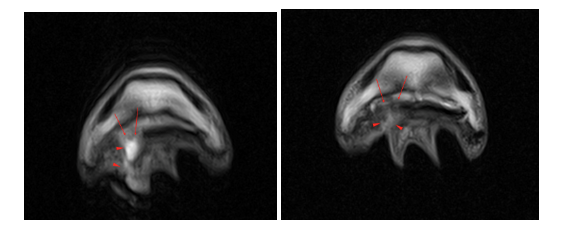

Follow-up MRI

Repeat MRI a fortnight later (right image) revealed the draining tract to be larger (red arrowheads) compared to previous (left image) on the T2FSE frontal images. Additionally, a distinct loss of integrity of the lateral part of deep digital flexor tendon towards its insertion was visible (red arrows). This loss of integrity to the tendon was present from the level of the navicular bone to the insertion on the distal phalanx.